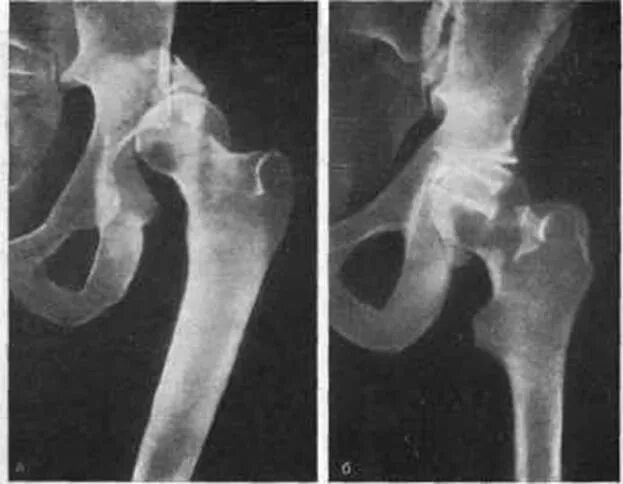

Склероз вертлужной впадины